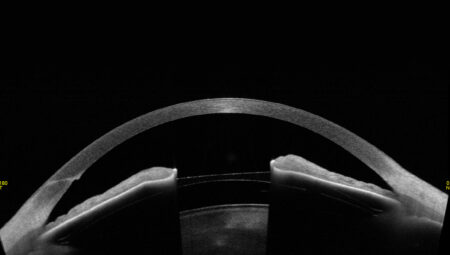

- zaawansowane obrazowanie ze zwiększoną głębią obrazowania (13mm) i prędkością skanowania (50.000 A-scan/sek),